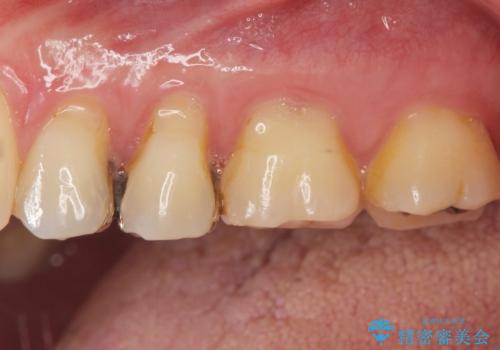

- 銀歯を白くしたい。水が少し染みるとの事で来院。

歯と歯茎の境目にプラスチック樹脂の治療の後があり、そこが染みる原因となっていました。

拡大鏡下で銀の詰め物、古いプラスチックの樹脂を外し、虫歯が残ってないかを確認して

ジルコニアクラウンで治療を行いました。